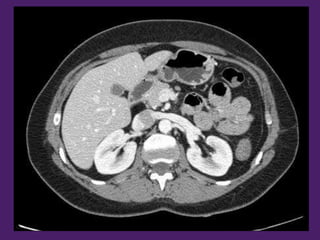

Riñón derecho Riñón izquierdo

Páncreas

Vesícula biliar

Píloro

Colon descendente

Antro

gástrico

Arteria

renal

izquierda

Vena renal izquierda

Arteria mesentérica superior

Primera porción

del duodeno